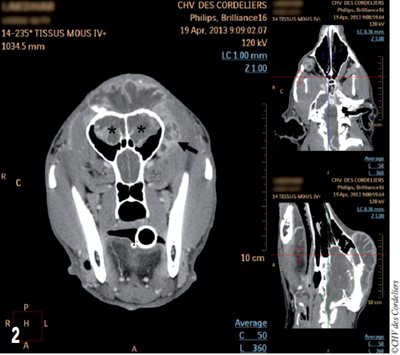

- Rostralement, la masse recouvre les sinus frontaux dorsalement et les envahit (photo 2).

- Caudalement, le tissu hyperdense après l’injection de produit de contraste s’étend jusqu’au milieu de la crête occipitale.

- Latéralement, la masse déborde de façon plus importante du côté gauche avec un envahissement du processus zygomatique de l’os frontal et s’étend 1 cm en arrière de l’œil (photo 3).

Photo 2 : Aspect tomodensitométrique de la masse : notez l’envahissement des sinus frontaux (étoiles) et la latéralisation à gauche (flèche).

Aucune compression du cerveau n’est visible au scanner.

Les images thoraciques ne mettent pas en évidence de métastase à distance.

Photo 3 : Aspect tomodensitométrique de la masse en vue sagittale : la masse s’étend très caudalement (flèche).